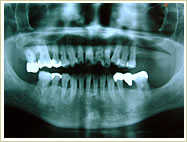

症例 63歳 女性 インプラント埋入数:2個 1本 画像拡大

治療前 治療後